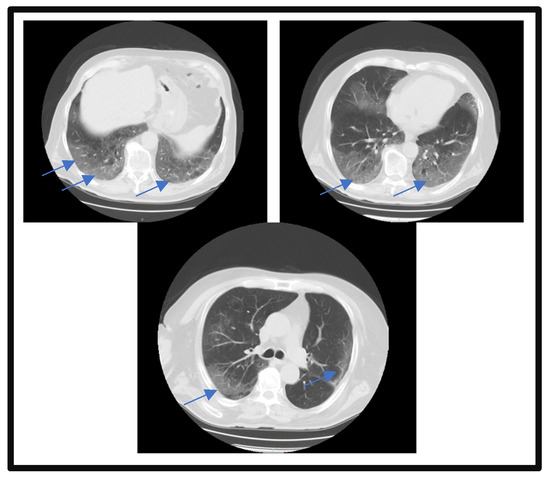

2. Case Report